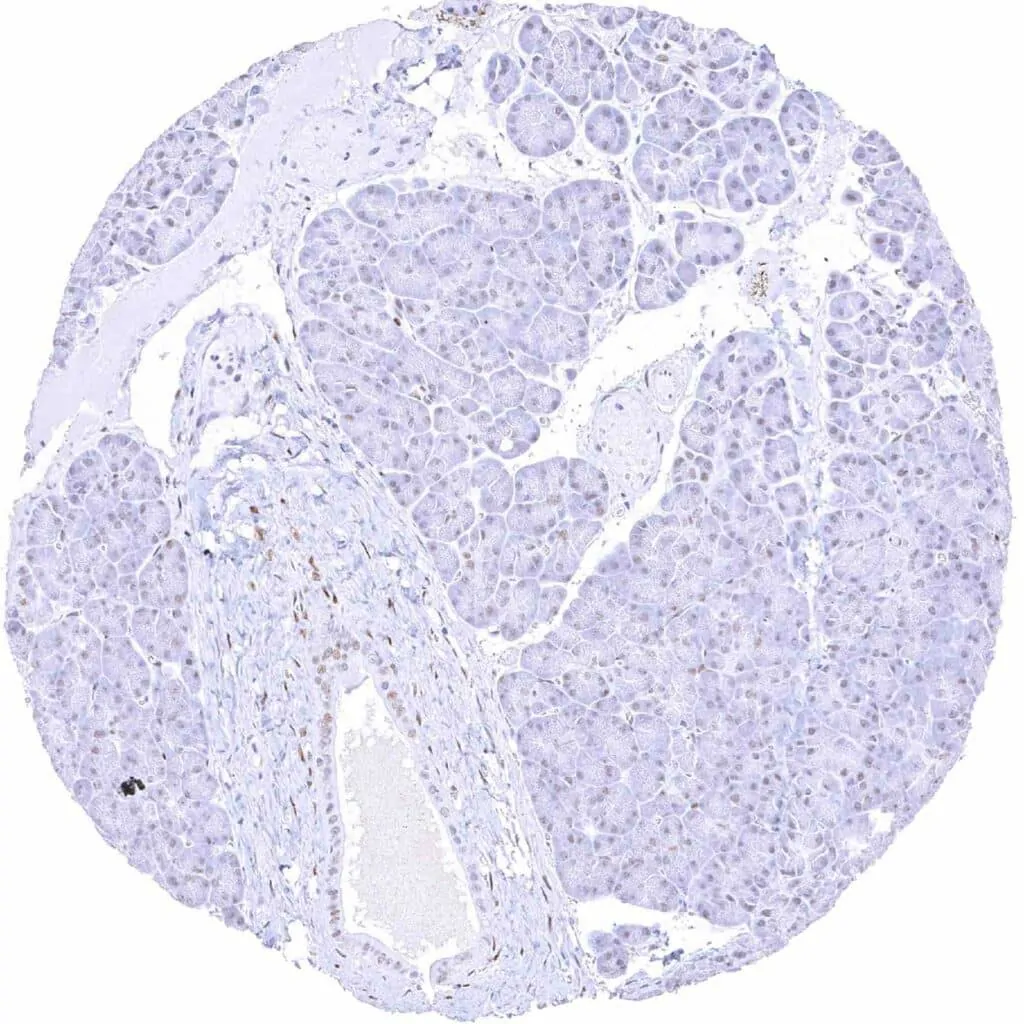

Pancreas – Weak to moderate TLE1 staining of acinar and ductal cells

Pancreas – Weak to moderate TLE1 staining of acinar cells and of most islet cells